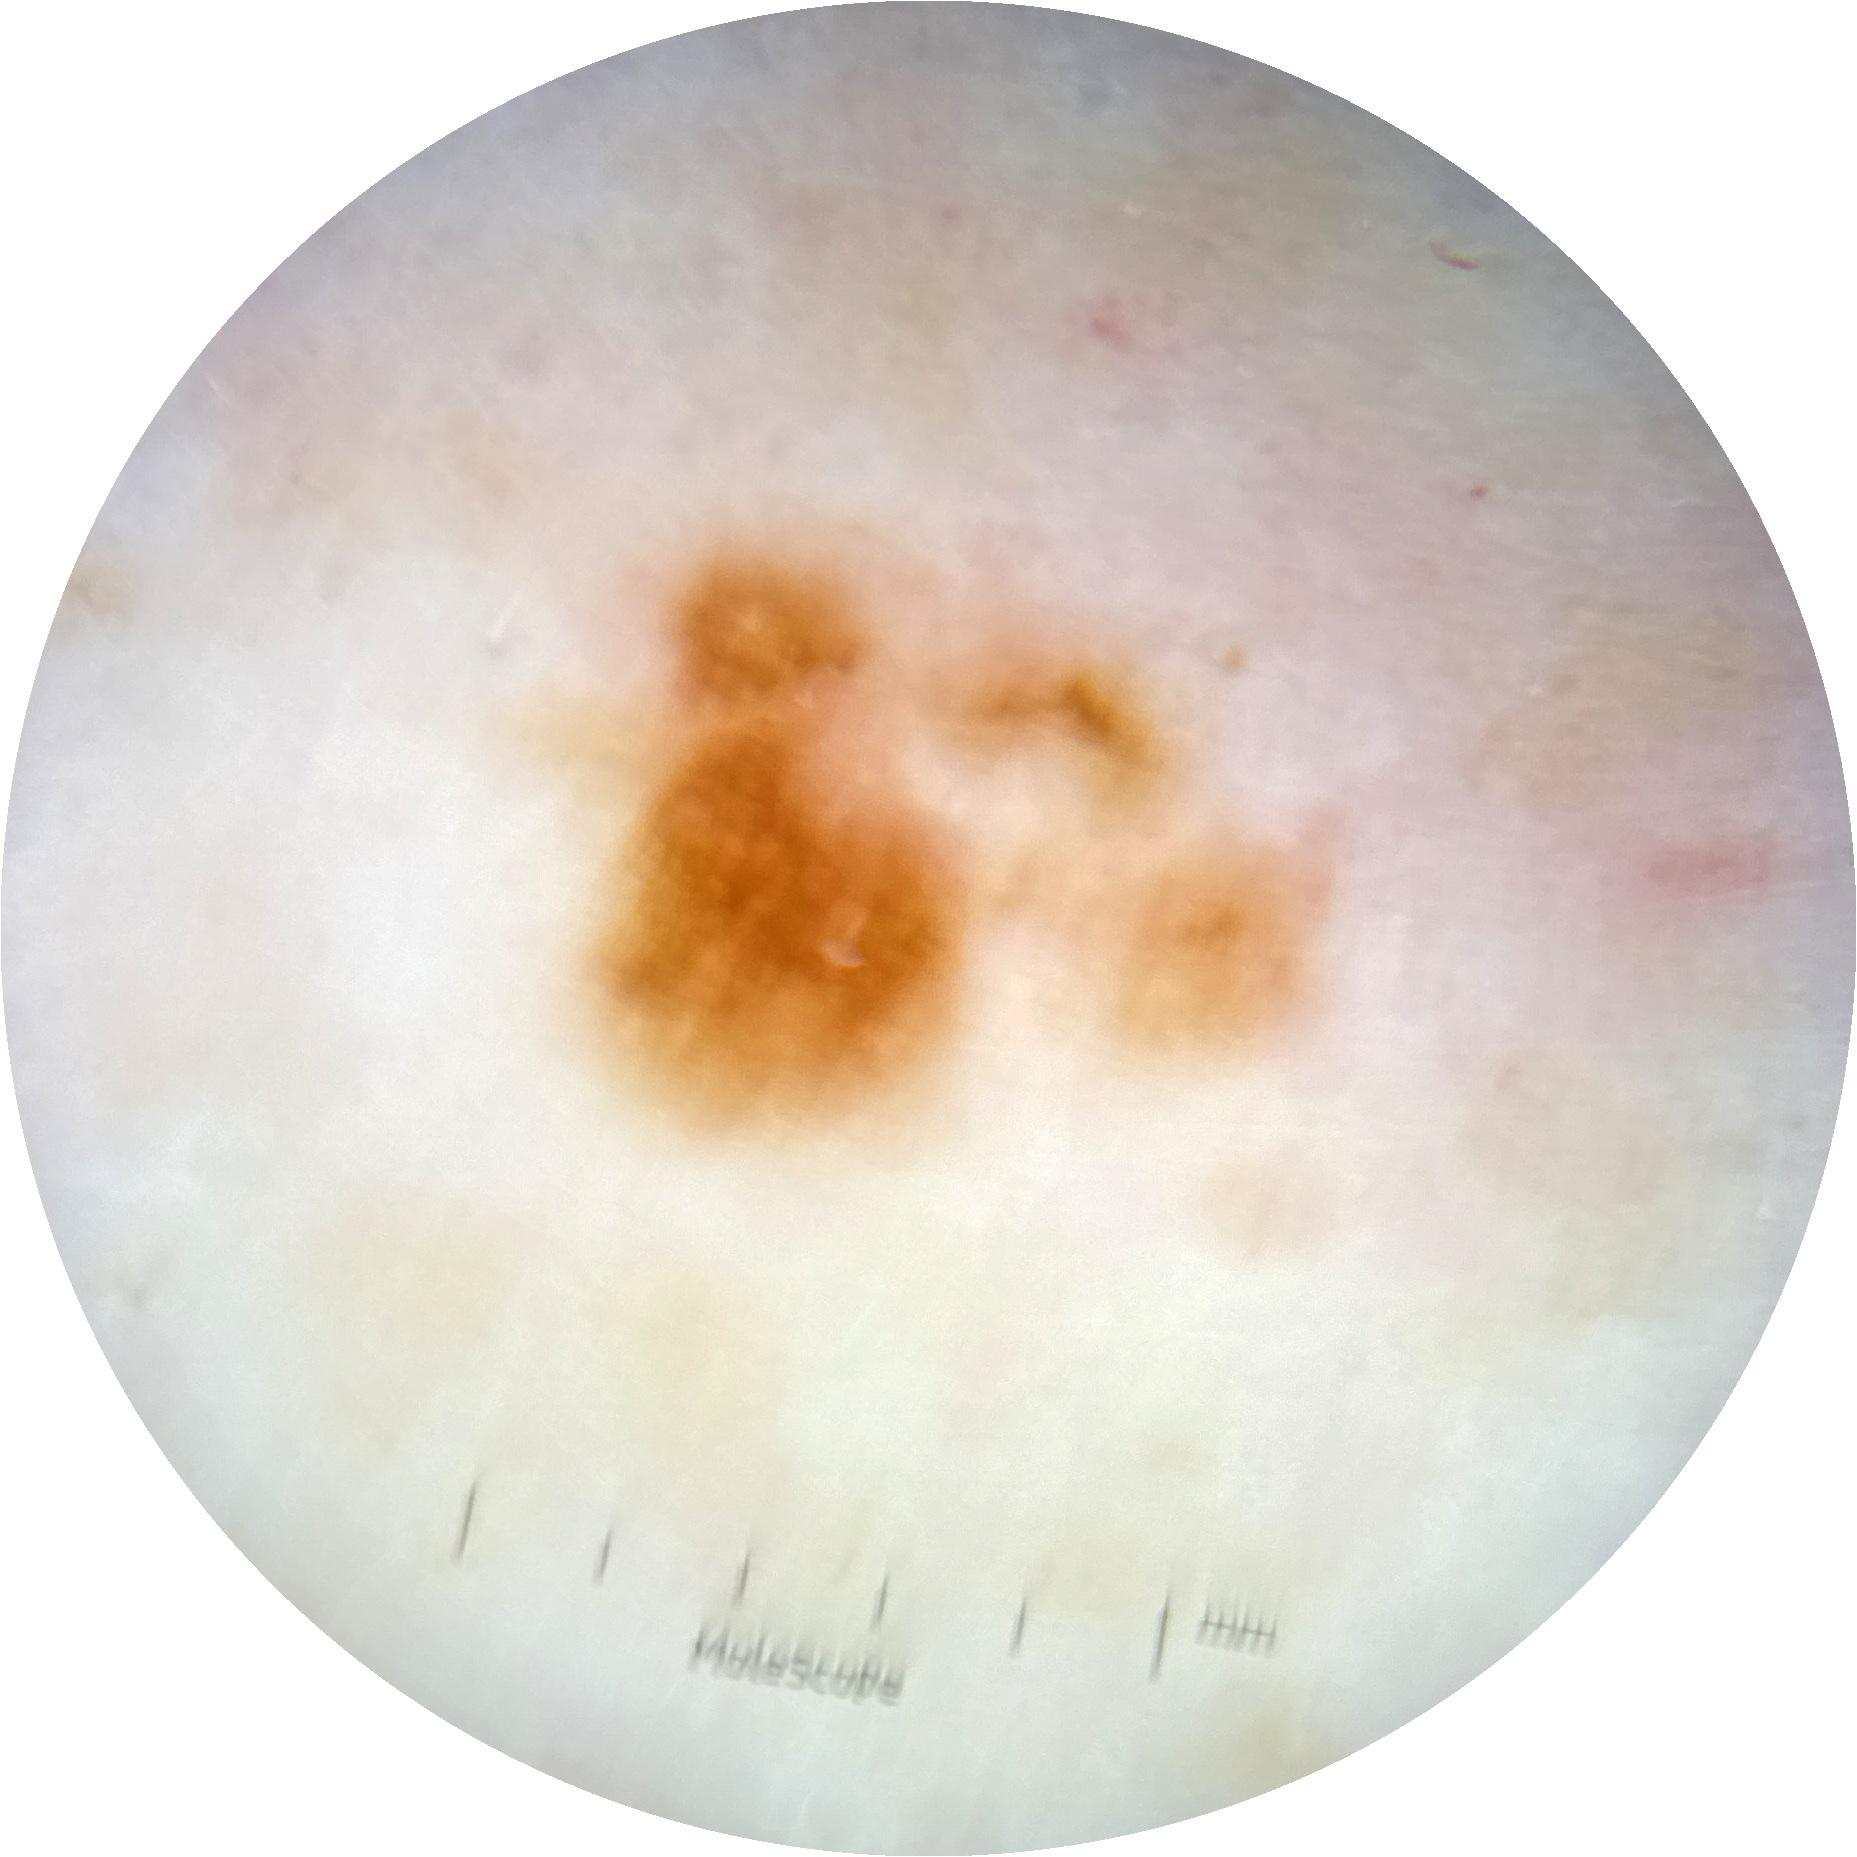

ISIC_2507441

2423 x 2423

Clinical

Field Value

acquisition_day 0

age_approx 60

anatom_site_1 Trunk

anatom_site_2 Posterior trunk

anatom_site_general posterior torso

diagnosis_1 Benign

image_manipulation instrument only

image_type dermoscopic

lesion_id IL_2667319

patient_id IP_4084217

sex male